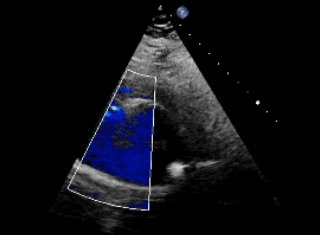

术前超声、造影

超声下可见右冠窦与右心房相通,主动脉短轴切面示类似膜周部室缺